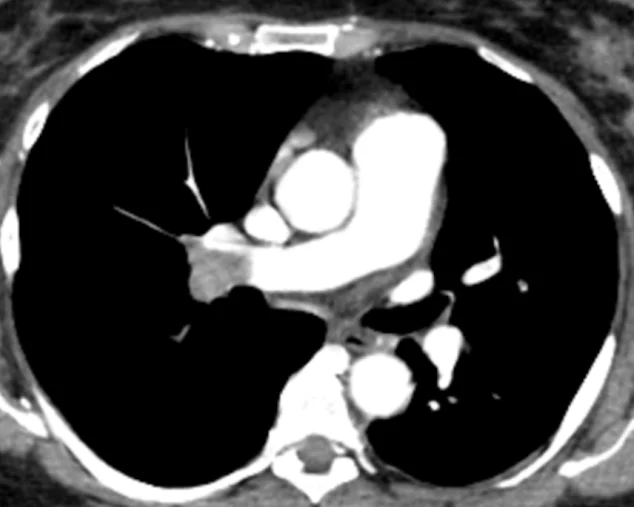

Figure 2. Axial Contrast – Enhanced CT Pulmonary Angiography (CTPA)

This axial contrast – enhanced CT image of the chest demonstrates a filling defect within the pulmonary arterial system, consistent with acute pulmonary embolism.

Key Radiologic Findings:

- A hypodense intraluminal filling defect is seen within a contrast – opacified pulmonary artery (likely at the lobar or segmental level).

- The thrombus is surrounded by contrast material, producing the classic ‘Polo mint sign’ (central defect with peripheral contrast)

- The involved artery may appear slightly expanded, suggesting an acute process.

- The adjacent lung parenchyma appears relatively preserved, without clear infarction in this slice.

Clinical Significance:

- This image confirms the diagnosis of acute pulmonary embolism (PE).

- In the context of subclavian venous thrombosis (Figure 1), this represents a proximal embolic complication.

- Acute PE can lead to: Increased pulmonary vascular resistance, right ventricular strain, and potential hemodynamic instability

Diagnostic Contribution:

This figure is critical for:

- Establishing a definitive CT scan diagnosis of pulmonary embolism

- Demonstrating the direct intravascular clot rather than indirect signs

- Supporting urgent initiation of anticoagulation or thrombolytic therapy

Radiology Insight (Expert Level):

- Acute emboli typically form acute angles with the vessel wall

- Chronic emboli (not seen here) would show: Eccentric location, Wall – adherent thrombus, Possible calcification